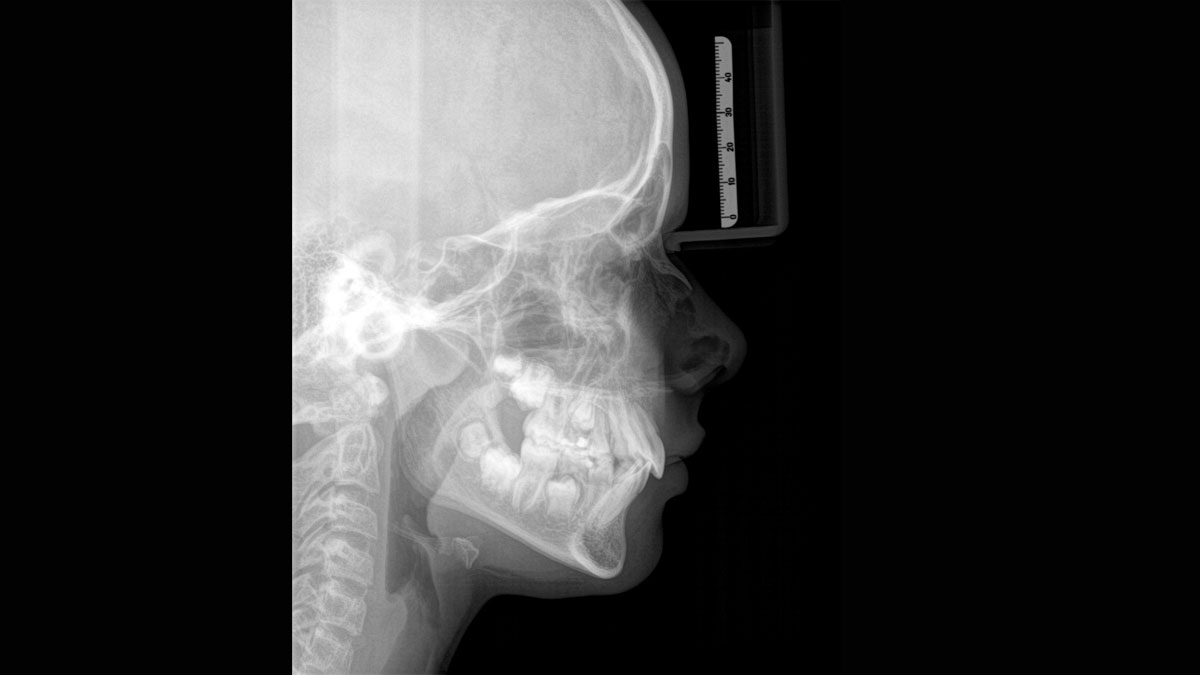

El equipo de radiología 2D/3D de alta calidad con una amplia gama de servicios para cada clínica. Ya sea como un dispositivo puramente 2D o como un módulo 3D, el Orthophos S es un socio confiable y está optimizado para las tareas diarias. Su sensor CsI Plus con función de autofoco garantiza imágenes claras, incluso en casos anatómicamente difíciles. El posicionamiento automático del paciente junto con el bloque de mordida oclusal patentado permite un posicionamiento del paciente fácil y que ahorra tiempo. Para su uso en ortodoncia, la Orthophos S también está disponible con un brazo cefalométrico opcional. Y como para Dentsply Sirona es importante estar preparado para el futuro, el brazo cefalométrico se puede reacondicionar en cualquier momento.

El brazo cefalométrico puede añadirse en el lado derecho o izquierdo de la unidad y solicitarse en el momento de la compra o instalarse en cualquier momento